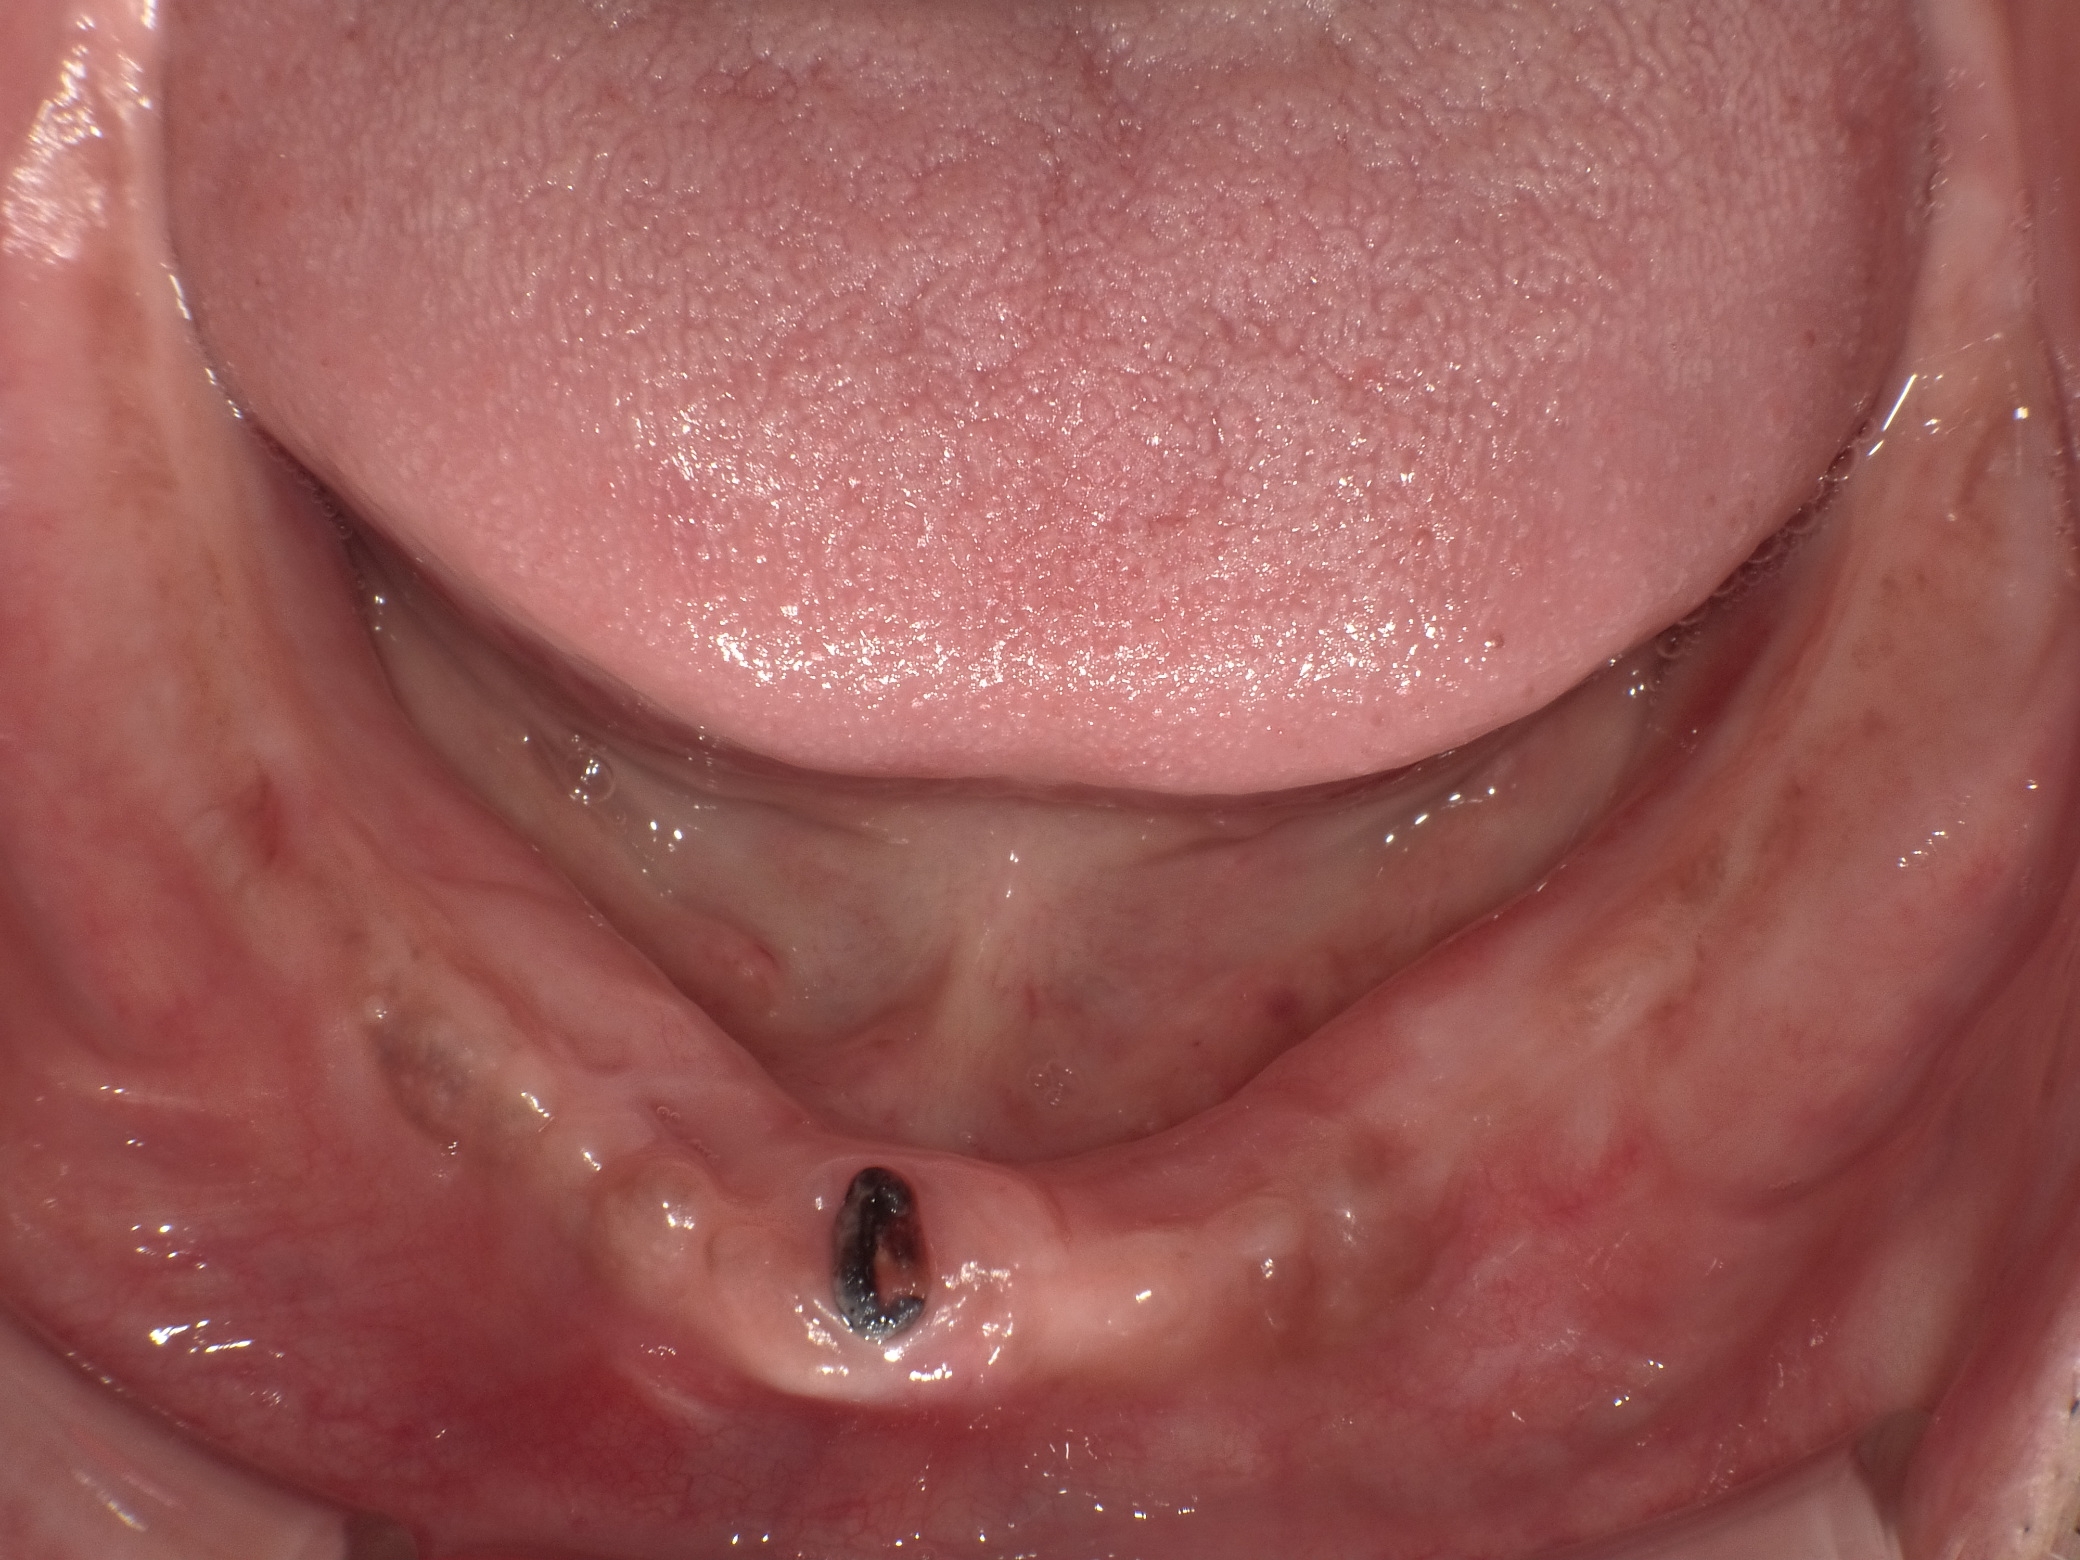

インプラントオーバーデンチャー症例

主訴 しっかり噛んで美味しいものを食べたい(男性) 治療内容 保存不可能な歯を抜歯後、2本のインプラントを埋入。

インプラントのアタッチメントと入れ歯の留め具とで凹凸接続し、動かない快適な入れ歯を装着しています。治療期間 約4ヶ月 費用 総額 ¥880,000–(税込) リスクと副作用 ・外科治療となるので、お身体の状態によっては受けれない場合がある(広範囲に適用可能な治療ですが、個々の患者様の状況によって適用外な場合もある)

・術後に多少の痛みや腫れが出ることがある